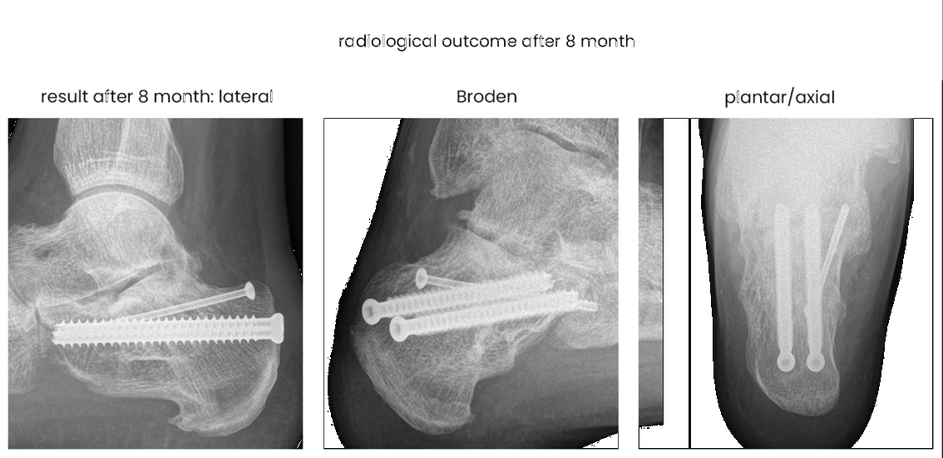

case 17BD, 47 years old, male, fall during work, 2 meters, "comminuted fracture", surgery after 2 days